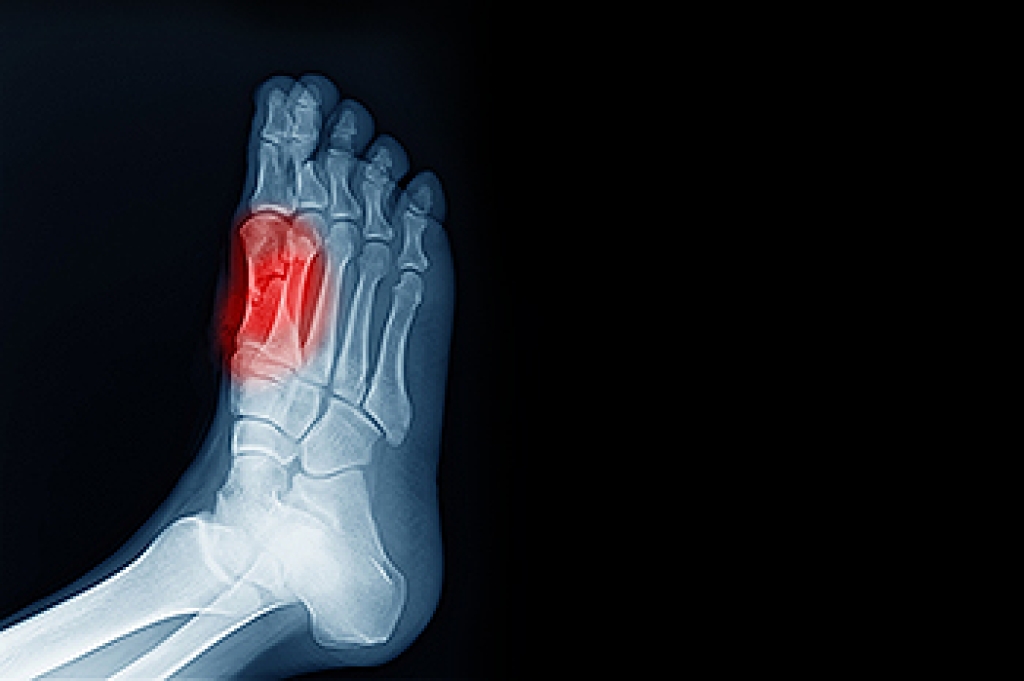

Heel pain is often associated with plantar fasciitis. The plantar fascia is a band of tissues that extends along the bottom of the foot. A rip or tear in this ligament can cause inflammation of the tissue.

Heel spurs are another cause of pain. When the tissues of the plantar fascia undergo a great deal of stress, it can lead to ligament separation from the heel bone, causing heel spurs.